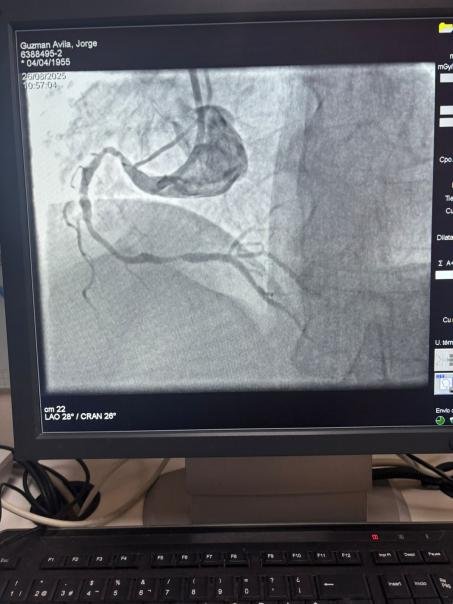

Siamo orgogliosi di condividere un caso straordinario dell'ospedale Sótero del Río, Cile, dove il Dr. Martín Valdebenito ha trattato con successo una lesione fortemente calcificata nell'arteria coronaria destra (prima curva) utilizzando il nostro sistema di catetere di dilatazione del palloncino Vesscrack Coronary IVL.

La procedura ha ottenuto risultati eccezionali, con la regione calcificata effettivamente incrinata e il flusso della nave ripristinato. Questo segna un'altra pietra miliare nell'espansione dell'accesso globale a soluzioni avanzate per la calcificazione coronarica complessa.

Il confronto tra le immagini angiografiche pre-procedura e post-procedura dimostra chiaramente il significativo impatto clinico della nostra tecnologia IVL.